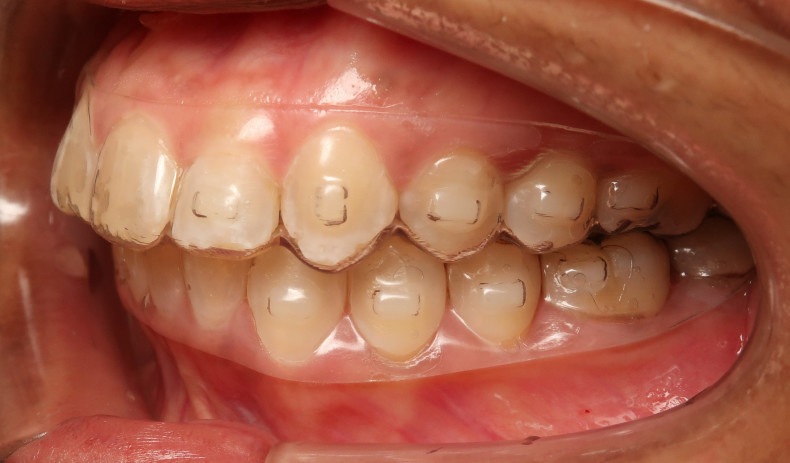

Der intraorale Befund (Abb. 2a–e) sowie die Modellanalyse (Abb. 3a–e) zeigten neben dem Diastema mediale im Oberkiefer vor allen Dingen eine Anteinklination und Supraokklusion beider Fronten. Besonders anterior wiesen beide Zahnbögen eine transversale Enge auf. Dies zeigte sich in einem deutlichen Unterkieferfrontengstand mit Labialkippung des Zahnes 41. Neben Abrasionen und Schlifffacetten, vor allem in der Front, waren auch vereinzelt Gingivarezessionen erkennbar. An Zahn 11 lag eine Schmelzfraktur der Inzisalkante vor. Durch die zwangsgeführte Laterognathie ergab sich eine Mittellinienverschiebung nach rechts von 3 mm. Eine beidseitige Distalokklusion bei vergrößerter sagittaler (6 mm) und vertikaler (5 mm) Stufe war erkennbar. Aufgrund der deutlichen transversalen Zahnbogenenge im Unterkiefer ergab sich links eine Tendenz zum Scherenbiss.